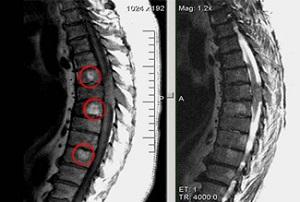

Врачи подчеркивают, что лечение рака позвоночника требует комплексного подхода и индивидуального выбора методов в зависимости от стадии заболевания и общего состояния пациента. Основными направлениями терапии являются хирургическое вмешательство, радиотерапия и химиотерапия. Хирургия может быть необходима для удаления опухоли и стабилизации позвоночника, особенно если есть риск компрессии спинного мозга. Радиотерапия используется для уменьшения размеров опухоли и облегчения болевого синдрома. Химиотерапия, в свою очередь, может быть назначена для системного воздействия на рак, особенно в случаях метастазов. Врачи также акцентируют внимание на важности реабилитации и поддерживающей терапии, которые помогают пациентам восстановить качество жизни после лечения. Современные методы диагностики, такие как МРТ и ПЭТ-КТ, позволяют точно оценить распространенность заболевания и выбрать наиболее эффективную стратегию лечения.

Лечение рака будет осуществляться онкологом на основании результатов биопсии, МРТ, рентгенографии и других диагностических процедур.